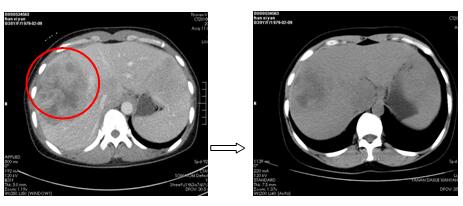

針對(duì)每一例化療患者,參照最新NCCN指南(為腫瘤診療的國(guó)際權(quán)威指南),為患者制定規(guī)范、有效的個(gè)體化化療方案。2周期化療后評(píng)價(jià)療效:其中1例肺癌肉瘤術(shù)后的胰腺占位的患者,2次化療后胰腺占位基本消失,另有1例非小細(xì)胞肺癌伴肺、心包、肝多發(fā)轉(zhuǎn)移患者,2次化療后肺部、肝內(nèi)病灶顯著縮小,其余化療患者還未到療效評(píng)價(jià)時(shí)機(jī)(指南推薦每2周期評(píng)價(jià)化療療效)。

圖1. 2周期化療后胰腺區(qū)占位基本消失